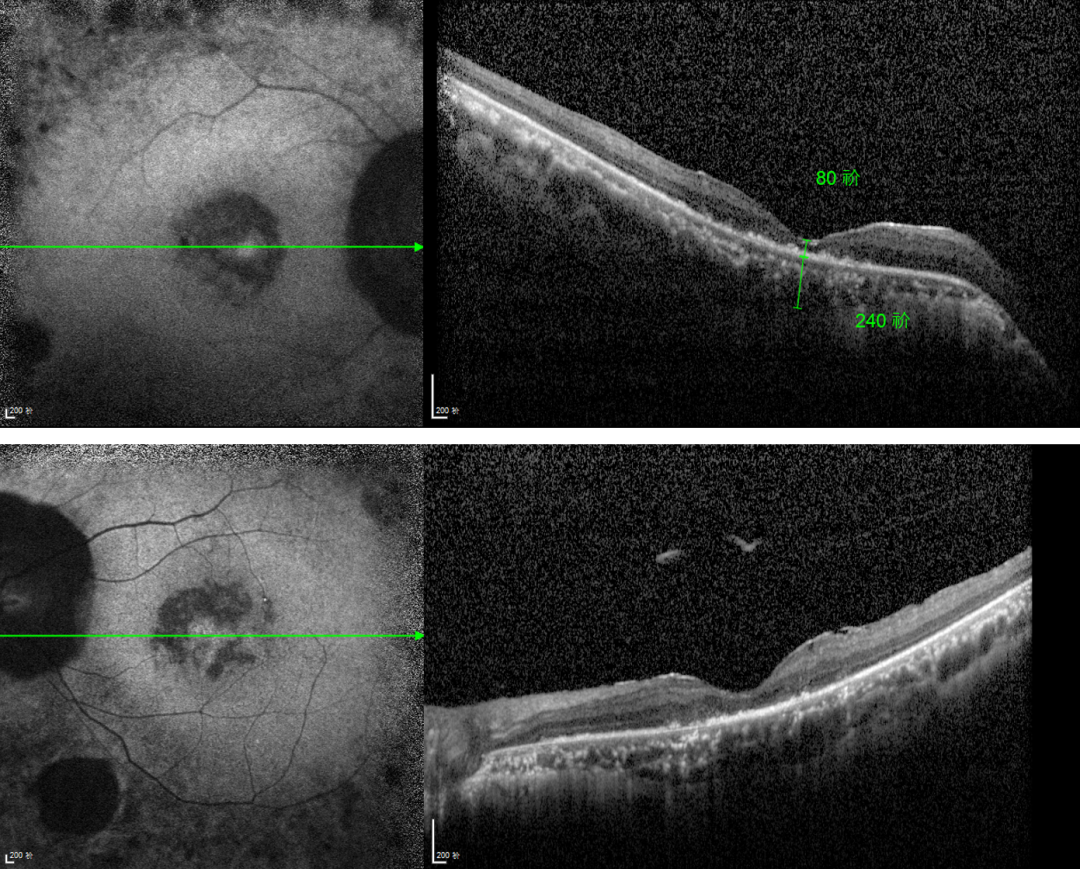

RP的診斷主要依靠眼底檢查、視野檢查、視網(wǎng)膜電圖(ERG)和基因檢測。眼底檢查可見典型的"骨細胞樣"色素沉著,ERG顯示視網(wǎng)膜功能下降,基因檢測可確定具體的突變基因。

視網(wǎng)膜色素變性